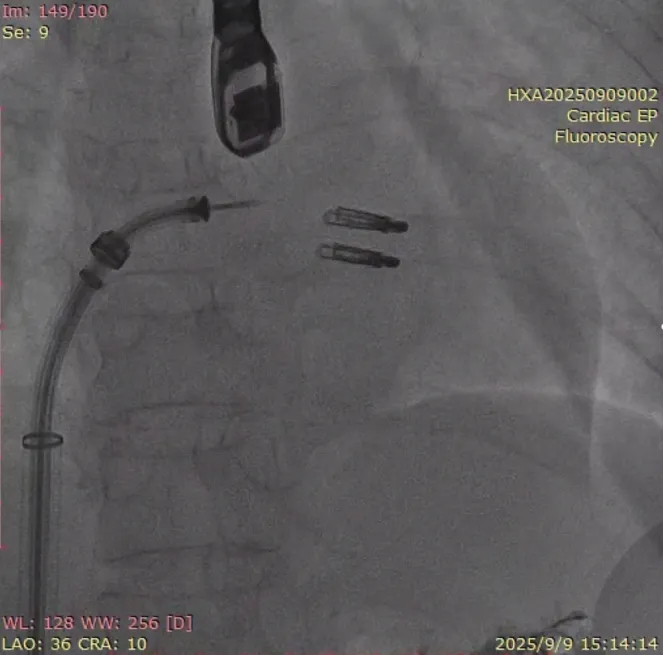

在经股静脉途径的TEER手术时,房间隔穿刺是一个很重要的基础步骤。有时候房间隔组织较韧较厚(多见于房间隔短穿刺位置需要靠后,或者外科房间隔修补术后),穿刺针通过之后要通过导引大鞘(GC)存在着较大困难,若强行推送大鞘可引起房间隔撕裂到左心房顶引起灾难性心包填塞。传统做法时使用外周球囊对房间隔进行扩张,但是不是每个导管室都常规配备外周球囊,且使用过大球囊仍可引起房间隔撕裂风险。我们提供了一种更简洁的方式,即使用导引鞘内芯和房间隔穿刺鞘两个管子(双管齐下)同时扩张房间隔穿刺口,再推送导引大鞘通过房间隔,无需额外器械,操作简单高效且安全(图1-4)。

图3. 沿着两根加硬导丝送入导引鞘内芯和房间隔穿刺鞘对房间隔进行扩张

图4. 顺利送入导引鞘通过房间隔